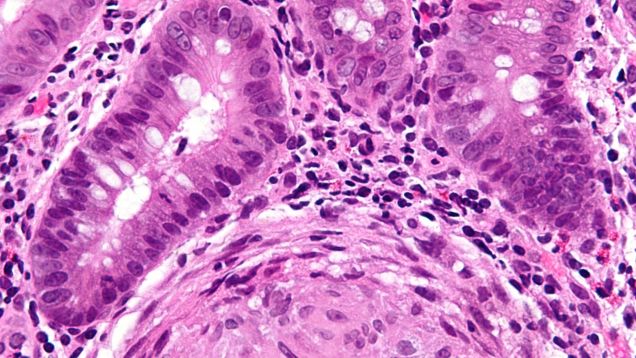

A fungal yeast found in cheese and other foods may wreak havoc in the guts of people with Crohn’s disease, according to new findings. In study published Thursday, researchers have found evidence that Crohn’s patients are much more likely to carry that yeast than the general public, and that this yeast is linked to…